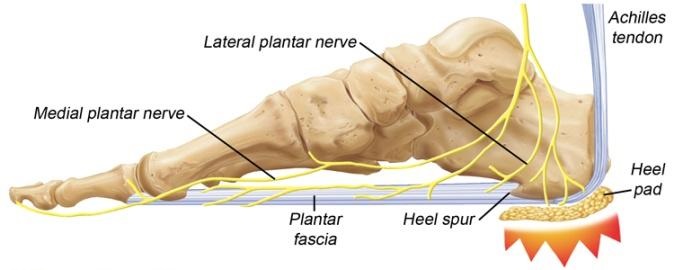

Heel Spurs – Feebo PLANTAR FASCIITIS (HEEL PAIN) - UDAI

PLANTAR FASCIITIS (HEEL PAIN) - UDAI  Heel Pain | Plantar Fasciitis Causes

Heel Pain | Plantar Fasciitis Causes  Plantar Fasciitis and Heel Spurs

Plantar Fasciitis and Heel Spurs  Plantar Fasciitis vs. Heel Spurs | Heel

What Is Plantar Fasciitis? Symptoms  Heel Spur Pain Also Called Calcaneal

Heel Spur Pain Also Called Calcaneal  Heel Spur VS Plantar Fasciitis

Heel Spur VS Plantar Fasciitis  10 Heel Pain Causes And When To See a

10 Heel Pain Causes And When To See a  Heel Spur Pain